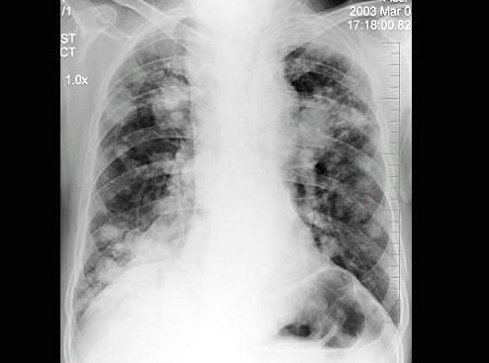

男,69岁,咳嗽,胸痛2月余,胸片检查如图,最可能的诊断为()

A.血行播散型肺结核

B.肺转移瘤

C.两肺炎症

D.细支气管肺泡癌

E.结节病